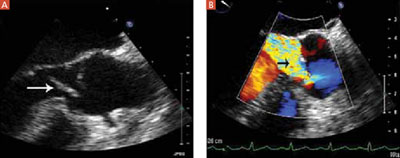

Surgery is scheduled immediately. A pre-operative transesophageal echocardiogram (FIGURE 3) confirms earlier findings and additionally reveals a small mitral valve vegetation. At surgery, the aortic valve is resected and replaced; a perivalvular abscess is drained.

FIGURE 3

Aortic valve vegetation, regurgitation

Transesophageal echocardiography image shows a vegetation on the coronary cusp of the aortic valve (A) and significant aortic valve regurgitation (B).